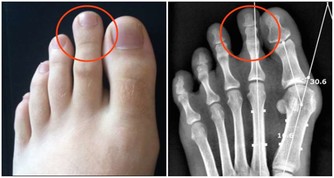

6、舌頭上出現明顯的病變或是囊腫

有時會是因為壓力所造成的現象,通常在1-2週內會自行痊癒,但是如果沒有好轉的跡象,請盡早就醫檢查,這可能是口腔癌的前兆。